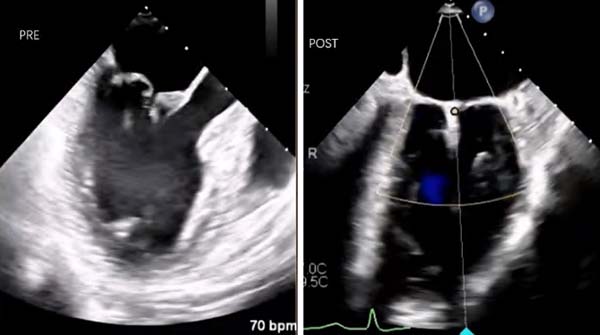

团队成功为一例巴洛综合征(Barlow综合征)合并重度二尖瓣关闭不全患者,实施经导管二尖瓣缘对缘修复术(TEER)。经股静脉TEER术已是朝阳医院常规开展的成熟技术,而巴洛综合征因心脏瓣膜质地脆弱、脱垂范围广,在技术开展初期被列为高风险“红区”病变,视为手术相对禁忌。朝阳医院在熟练开展“绿区”“黄区”常规病例TEER手术的基础上,借鉴国内外经验,成功攻克这一难题。患者为74岁女性,因突发呼吸困难无法平卧3天急诊入住CCU,有房颤、陈旧性脑梗及左侧偏瘫病史。检查显示其二尖瓣严重脱垂,导致重度关闭不全,心脏血液反流明显。经与家属充分沟通后,团队为患者实施TEER手术。在麻醉科、超声医学科精准配合与引导下,手术团队顺利置入两枚夹子修复瓣膜。术后复查显示,瓣膜脱垂问题完全解决,仅残余微量反流,无瓣膜狭窄情况。患者术后即刻清醒拔管,安返病房并顺利出院。

经导管二尖瓣缘对缘修复术(TEER)治疗巴洛综合征合并重度二尖瓣关闭不全患者相关影像